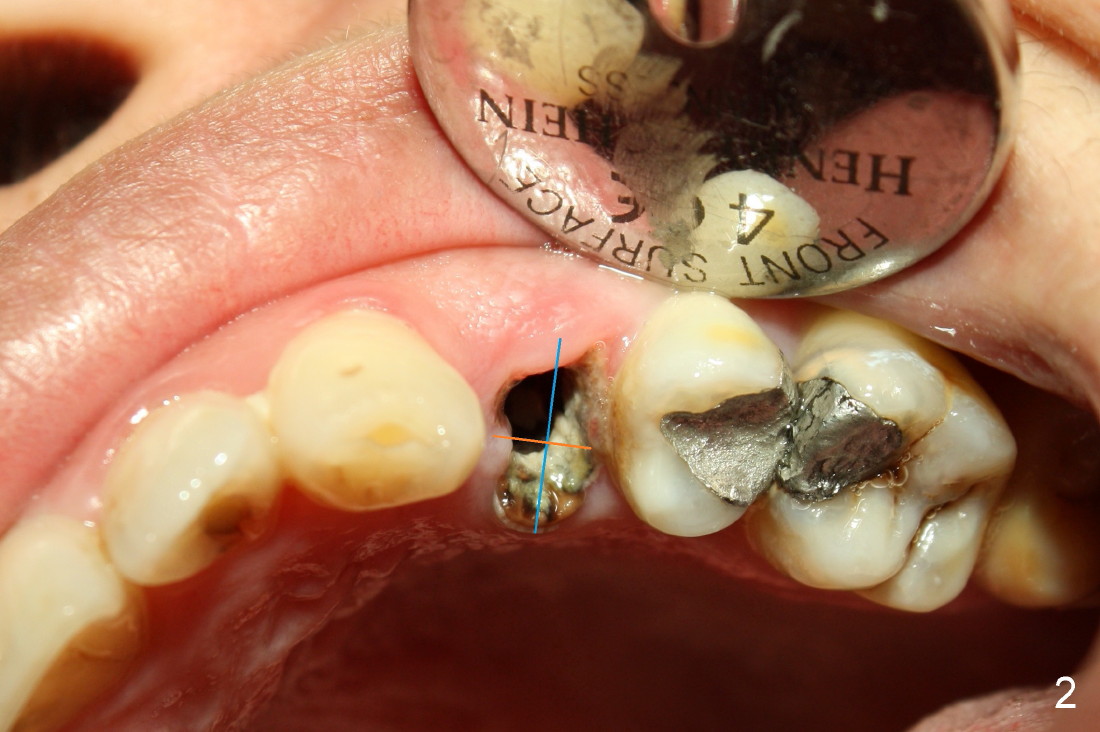

The second patient who is going to have an immediate implant in the upper bicuspid region is a 41-year-old lady. She is extremely scared of dental treatment. The second challenge is a periapical lesion associated with residual roots (Fig.1,2,4, as compared to freshly fractured tooth in the first case).

Fig.2 (occlusal view) shows the oval socket (buccolingual width vs. the mesiodistal one). It appears that when a rounded implant is placed, the buccal and lingual flaps should be raised and and advanced to close the socket (Fig.3).